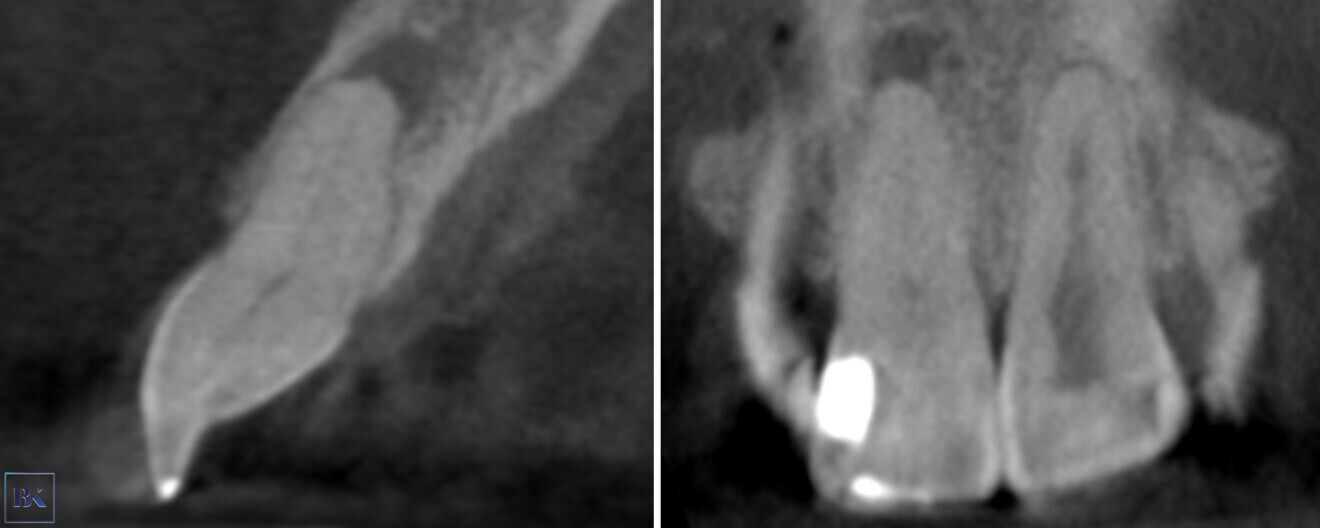

A 30-year-old female patient presented to the dental clinic complaining of constant pain of the left central incisor. Moreover, the patient was unhappy with the aesthetics of both incisors and had a history of trauma (Fig. 14). CBCT examination was performed with the 9000 C 3D (Fig. 15). The CBCT scan revealed a periapical lesion around the left central incisor and PCO for 12 mm from the incisal edge. The root of the left incisor was approximately 5 mm shorter than the root of the right incisor, which could indicate apical inflammatory root resorption. Moreover, PCO was present in the right central incisor up to 12 mm from the incisal edge, and an irregular shadow in the central area of the root was present. This image could indicate internal resorption. There was no lesion in the periapical area. In both teeth, the size of the canals in the periapical area were narrower than the typical size of the canals in the central incisors.

Fig. 14: Intra-oral view of the initial situation. Visible discoloration of the right central incisor.

Figs. 15a–c: CBCT scan, sagittal (a & b) and coronal planes (c). Pulp canal obliteration was visible in both teeth, and a periapical lesion was present around the left incisor. Internal resorption in the right incisor was suspected.